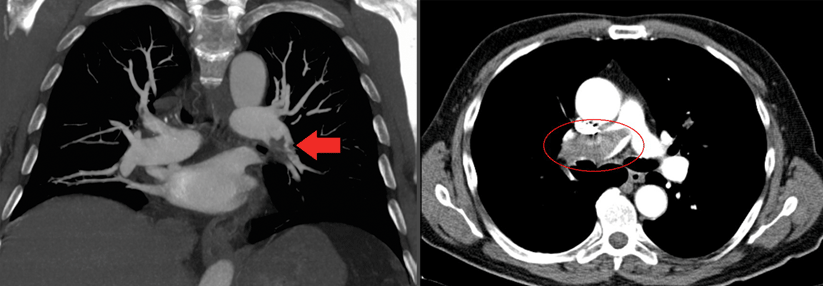

Ein 30-jähriger Patient mit massiver Adipositas wurde wegen starker Dyspnoe ins Krankenhaus eingewiesen. Die Spiral-CT zeigte eine Pulmonalembolie im linken Unterlappen und eine Pneumonie. Vor fünf Monaten hatte er schon einmal eine bilaterale Lungenembolie gehabt, berichtete Prof. Dr. Alexander Rosenkranz von der Nephrologie an der Universitätsklinik Graz, stellvertretend für Prof. Dr. Sabine Schmaldienst, Klinik Favoriten Wien. Damals war eine orale Antikoagulation mit einem Vitamin-K-Antagonisten für sechs Monate angesetzt worden. In der Familienanamnese fiel auf, dass der Vater des Patienten an einer Lungenembolie verstorben war.